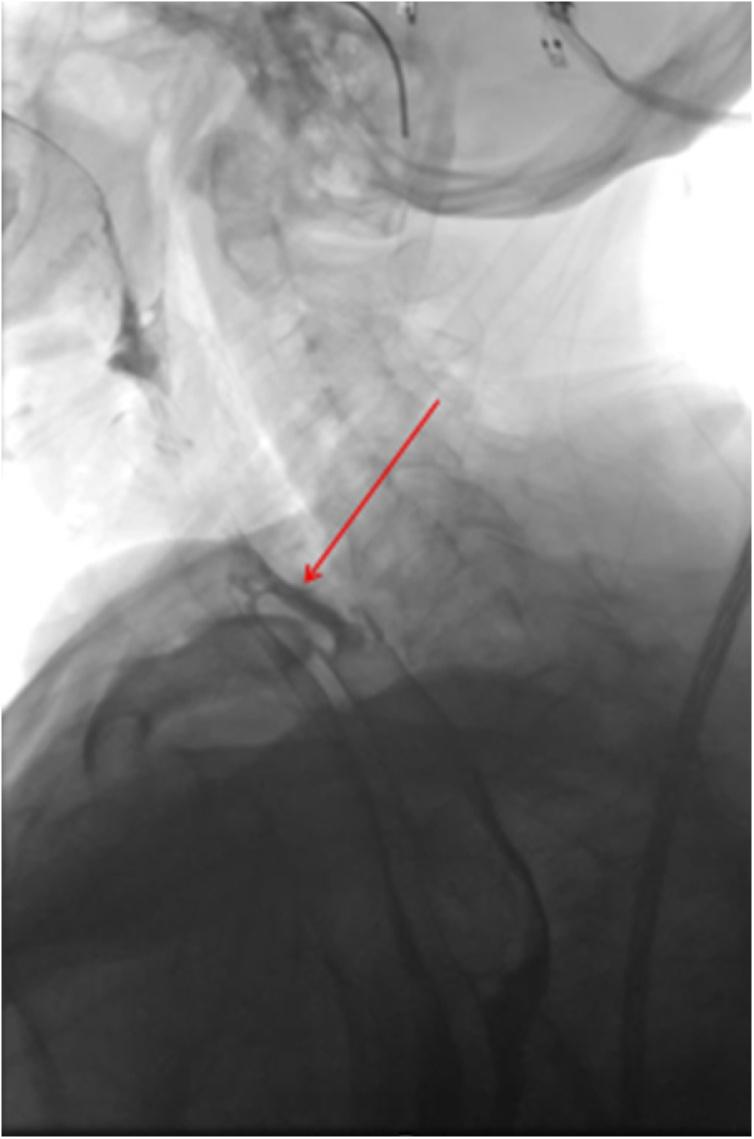

We described the case of a 79-year-old woman with an extremely rare case of Zenker's diverticulum perforation following a transoesophageal echocardiography and its successful management with a 6 months follow-up.

我们描述了一名79岁女性的病例,该患者在经食管超声心动图检查后发生极为罕见的Zenker憩室穿孔,并成功进行了治疗,随访6个月。